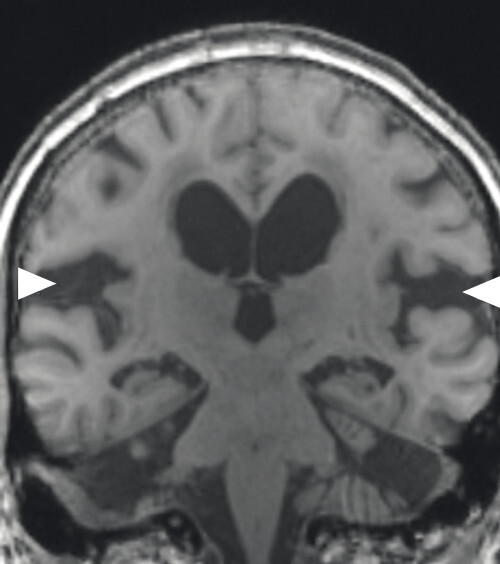

Abb. 69.4 Parkinson-Syndrome: Differenzialdiagnose Normaldruckhydrozephalus.

Typische Aspekte im MRT. Das DESH-Zeichen (a, Pfeile) ist am zuverlässigsten in Bezug auf das Erkennen des typischen Erscheinungsbilds eines Normaldruckhydrozephalus (a, b). Um ein weiteres typisches Zeichen, den spitzen Corpus-callosum-Winkel, verlässlich bestimmen zu können, ist es wichtig, den T1w 3-D-Datensatz exakt in der Commissura-anterior-Commissura-posterior-Linie zu orientieren (d, Pfeile) und den Winkel der Corpus-callosum-Schenkel in der koronaren Ebene auf Niveau der Commissura posterior (d, blaue Linie) zu bestimmen. Ein Corpus-callosum-Winkel von weniger als 90° gilt als anomal und als Hinweis auf den Aspekt eines Normaldruckhydrozephalus (e).

a DESH-Zeichen: disproportionale Erweiterung der inneren Liquorräume und der Sylvi-Fissur (Pfeile).

b DESH-Zeichen: enggestellte frontoparietale Liquorräume der Konvexität (s. auch a).

c Bei fortgeschrittenem Normaldruckhydrozephalus kommt es zusätzlich zu einer Liquordiapedese über die Ventrikelwände in das periventrikuläre Marklager, speziell im Bereich der Seitenventrikelvorder- und -hinterhörner (Polkappen).

d Spitzer Corpus-callosum-Winkel: Orientierung des T1w 3-D-Datensatzes exakt in der Commissura-anterior-Commissura-posterior-Linie (blaue Linie) und Bestimmung des Winkels der Corpus-callosum-Schenkel in der koronaren Ebene auf Niveau der Commissura posterior.

e Spitzer Corpus-callosum-Winkel: Beispiel eines pathologischen Corpus-callosum-Winkels.